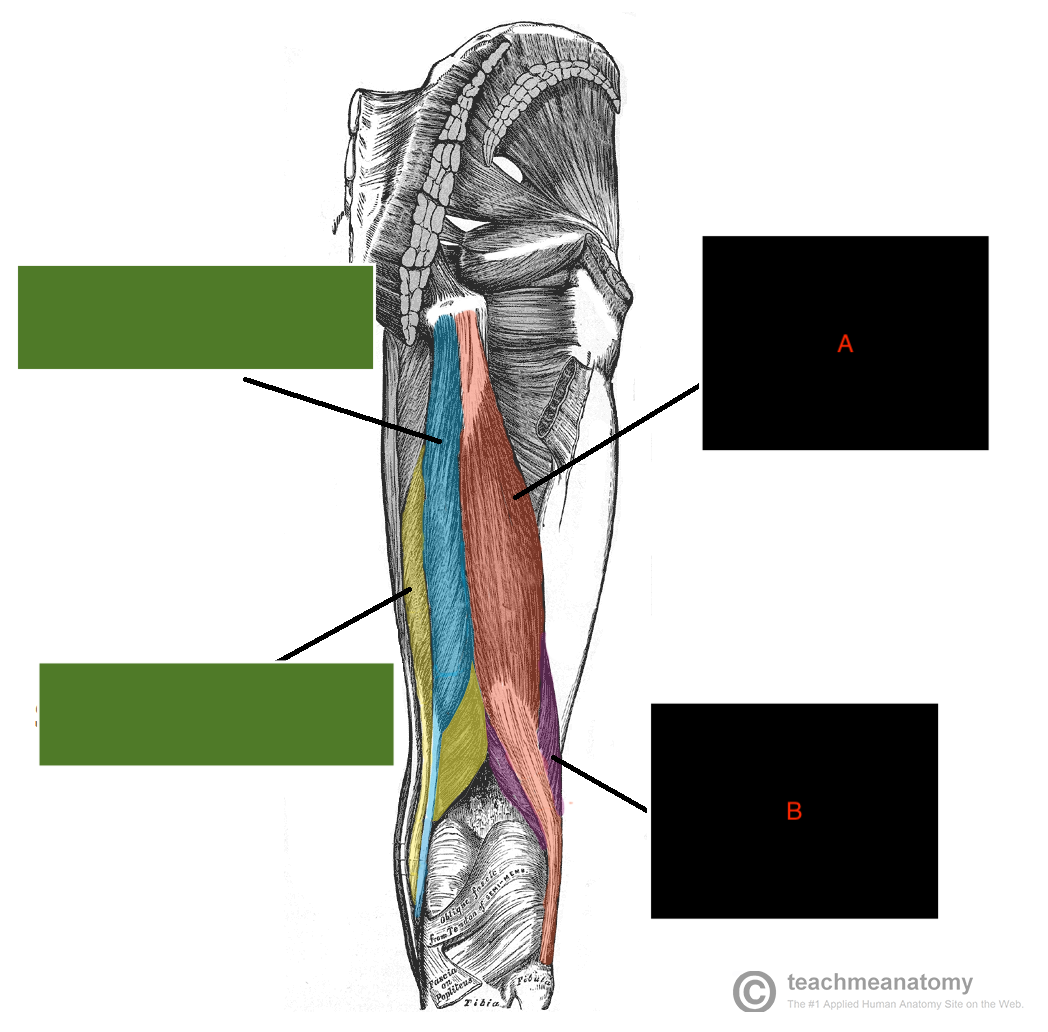

which muscle is A&B?

what are origins of A&B?

Bicep femoris

A - long head - comes from common hamstring - ischial tuboristy

B - short head - comes from posterior aspect of femur, laterally

where do the Biceps femoris, Semimembranosus & Semitendinosus attach ? (medially or laterally)?

Biceps femoris: laterally

Semimembranosus: medially

Semitendinosus: medially